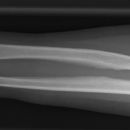

Unterarm

Unterarm a.p.

Patient sitzt seitlich am Tisch, Arm gestreckt und möglichst hochgelagert, damit der Ober- und Unterarm in gleicher Höhe liegen, Handrücken liegt auf (Supination). Bei distalem Unterarm (mit Handgelenk) Hand in Pronation. Bei proximalem und Unterarm total (mit EG) Hand in Supination.

Senkrecht auf Unterarm- und Filmmitte.

Ulnar und Radius dürfen sich nicht überkreuzen (bei prox. UA). Ein Gelenk muss immer mit abgebildet sein.